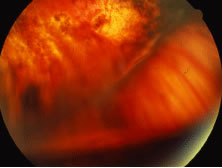

The ARN patient typically presents with progressive visual blurring in one or both eyes occurring over several weeks. These patients often are initially treated with corticosteroids, antitoxoplasmosis drugs, and other medications before arriving at the correct diagnosis. Examination reveals a prominent anterior uveitis that may be granulomatous or nongranulomatous (Fig. 1). Inflammatory signs may be prominent and cause severe pain (Fig. 2). The uveitis may be diffuse and so severe that it causes proptosis. These signs, and the diffuse vitreitis that makes the view of the retina difficult, may contribute to the high degree of delayed and/or misdiagnosis that occurs in the early stages of the disease. Significant vitreous cellular infiltration is seen in the presence of retinitis that is manifest by opacification of the retina, often most prominently in the periphery. Posterior pole involvement may include retinitis, as well as inflammation of the optic nerve head. Optic neuropathy might be the first sign of ARN with subsequent development of other retinal manifestations.8 Ultrasonography and computed tomography (CT) might be helpful in cases of ARN associated with optic nerve edema revealing enlargement of the optic nerve sheath.9 Even in ARN patients who are not immunocompromised and who have no clinical evidence of encephalitis, magnetic resonance imaging of selected cases has shown lesions of the lateral geniculate, optic tracts, and chiasma, which suggests that the virus spreads through the central nervous system (CNS) by axoplasmic transport from the retinal ganglion cells.10 A secondary retinal vasculitis is common, often accompanied by a mild number of retinal hemorrhages. Days to weeks after onset of the infection, the discrete peripheral lesions typically coalesce into a white or yellow ring of infected retina, and the associated vasculature is obliterated (Fig. 3). Necrotic retina desquamates into the vitreous resulting in vitreous sheets.3,6 Eventually, most untreated eyes can be expected to develop retinal detachment resulting from development of multiple full-thickness retinal breaks accompanied by traction or exudation.11 Giant retinal pigment epithelial tears have also been reported.12